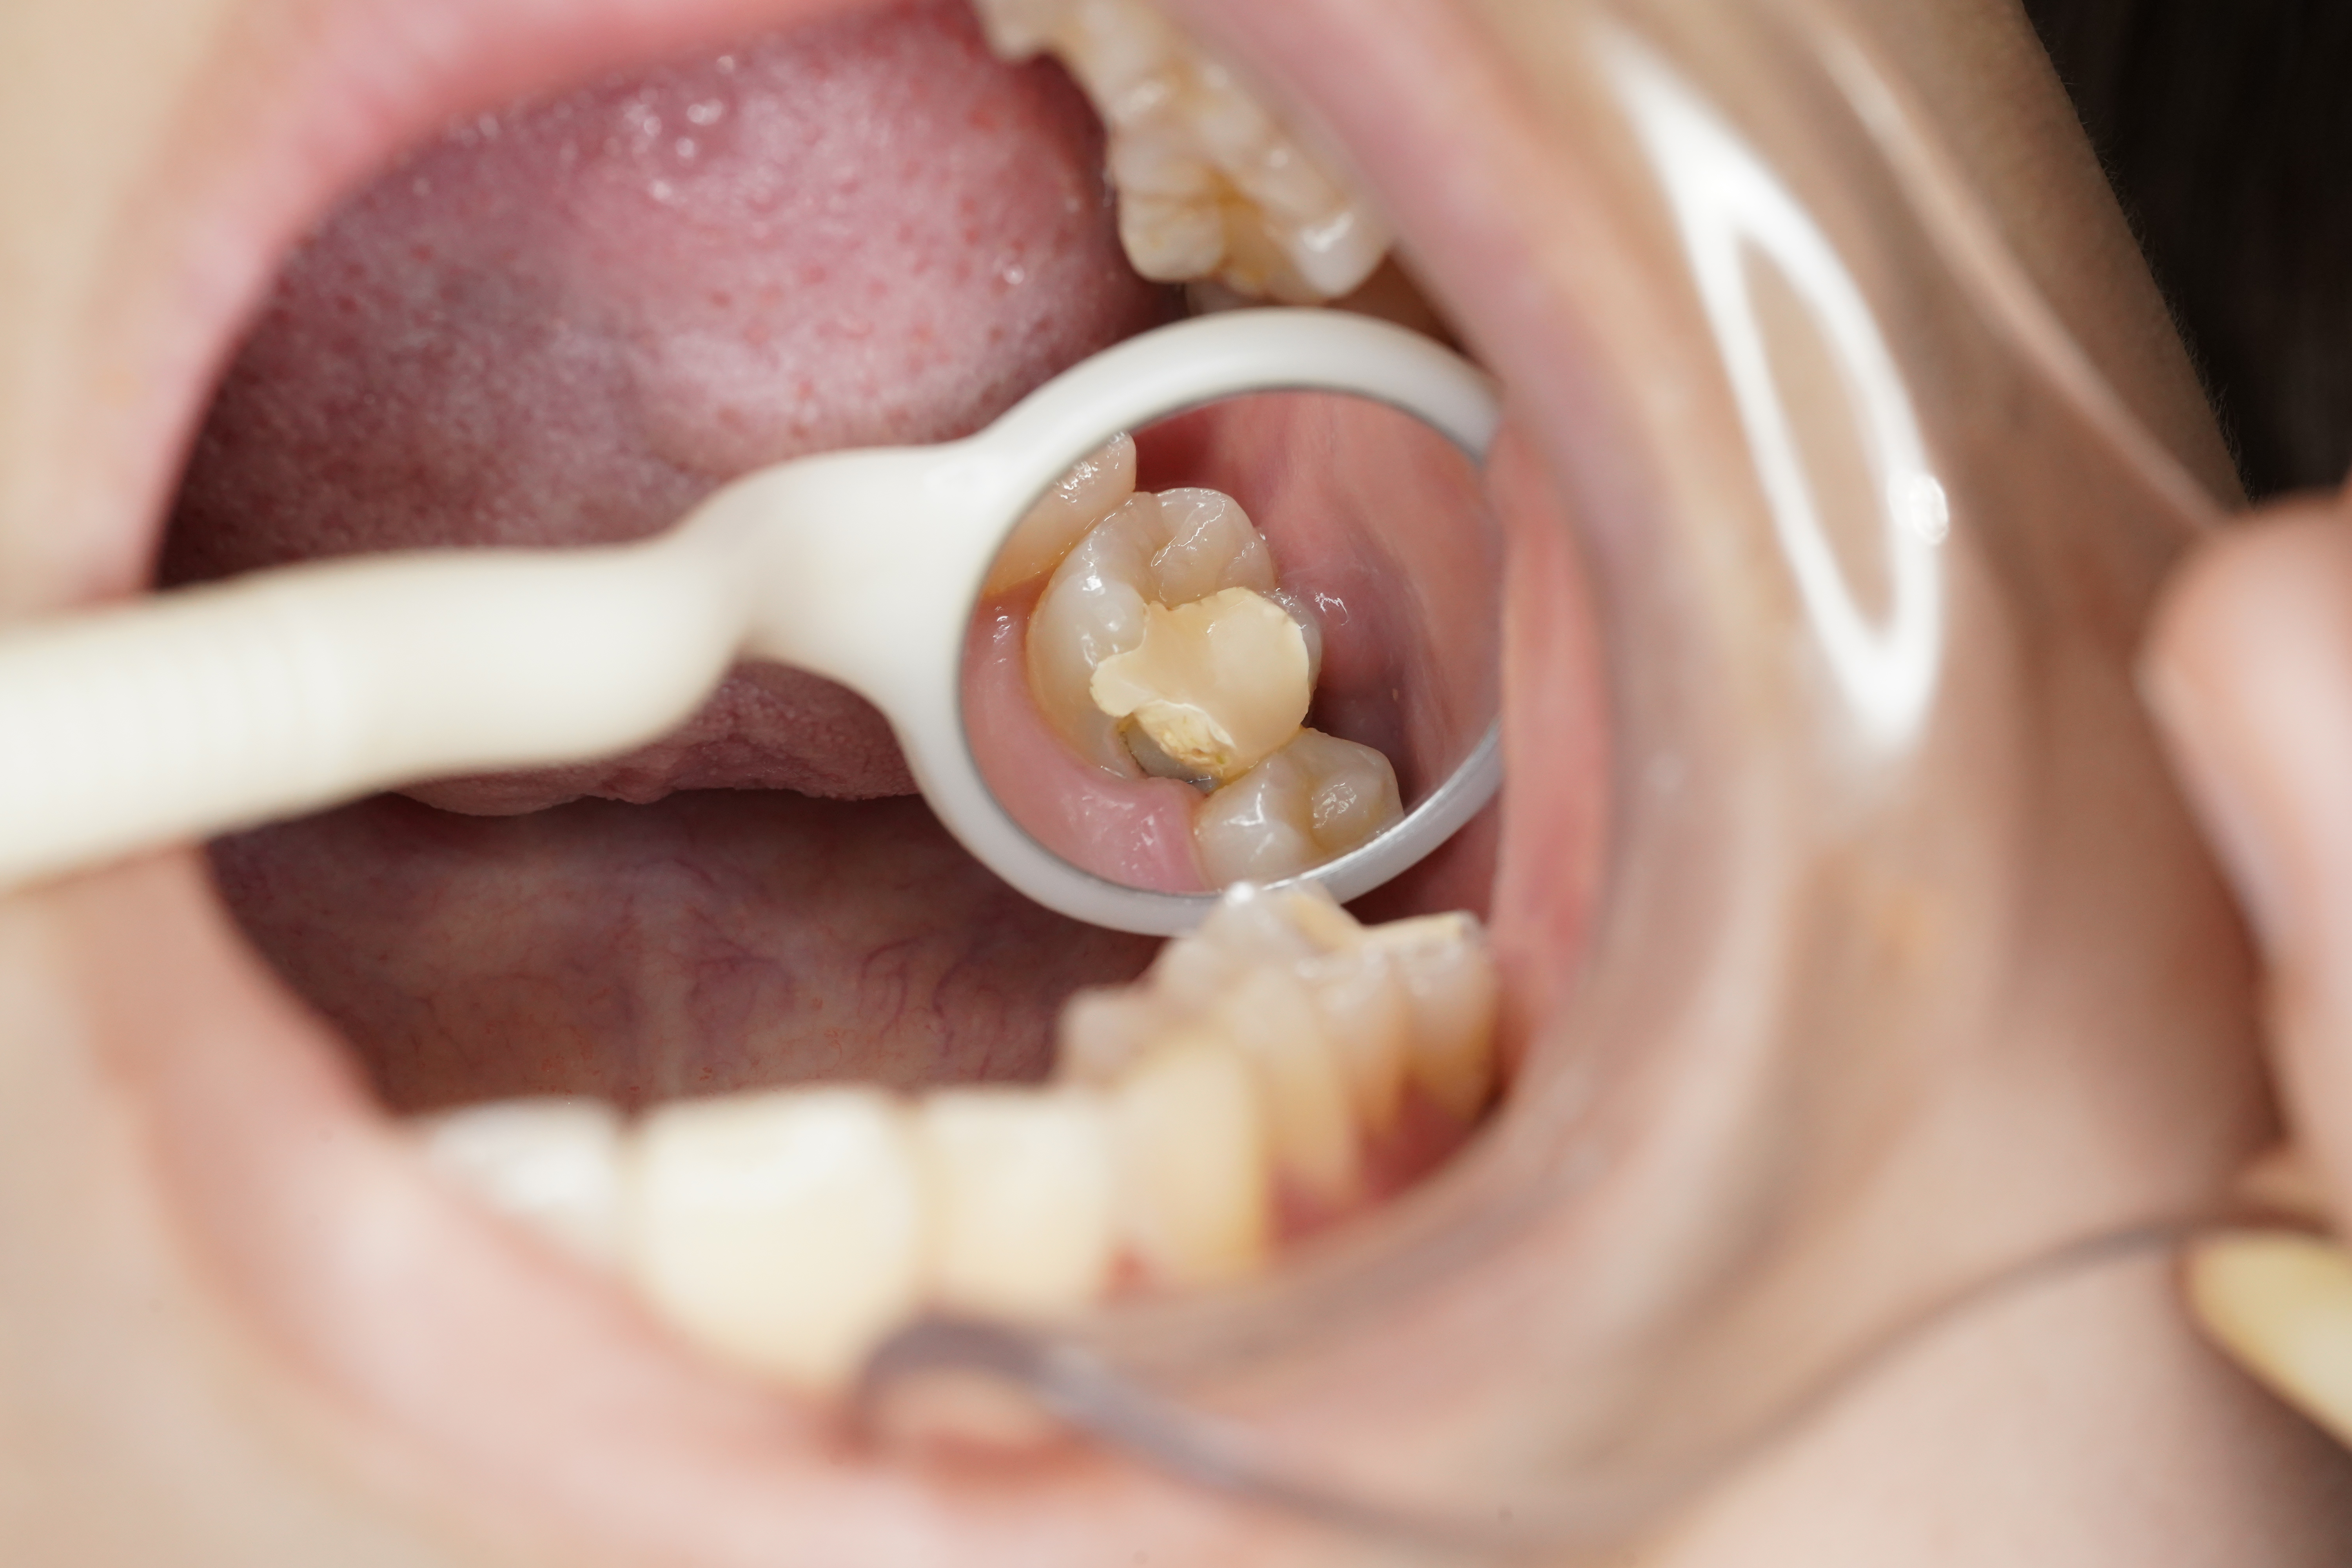

プラスチックを外し虫歯の状態を確認していきます。

中では虫歯がかなり大きくあることが次の画像からお分かりいただると思われます。